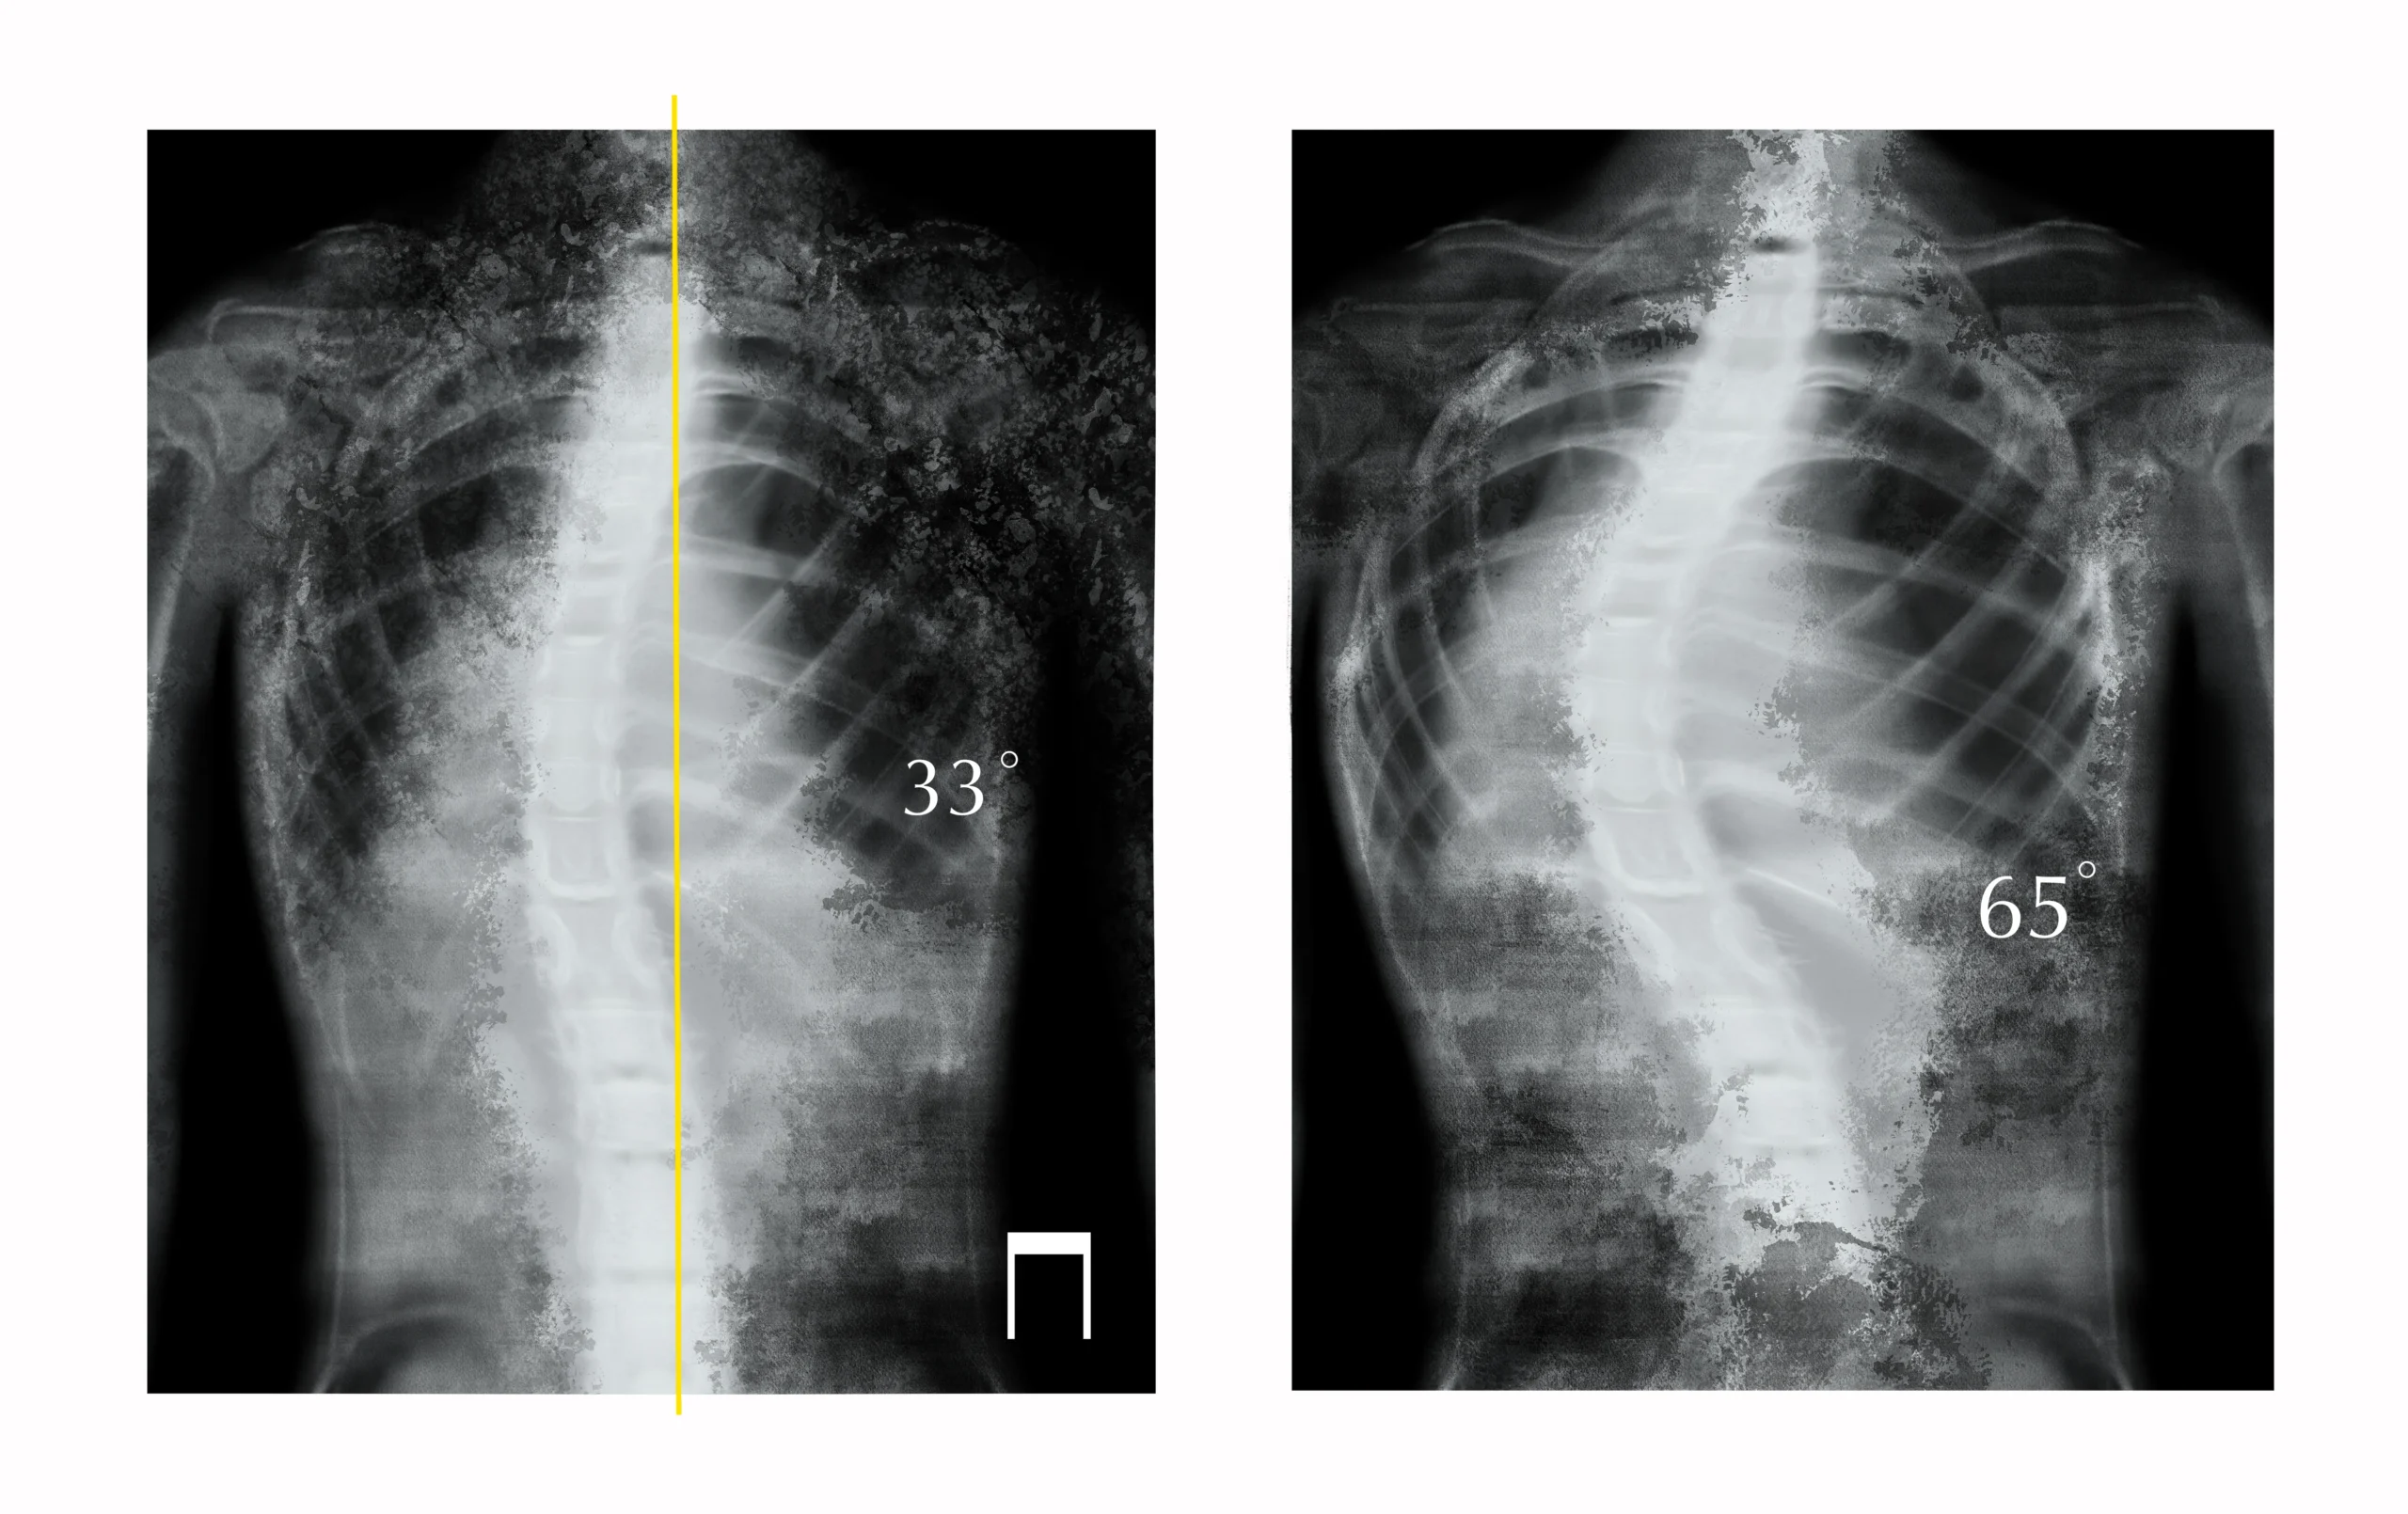

Kenali Perbedaan Antara Kifosis dan Skoliosis 11 Juni 2024 Tahukah Anda apa perbedaan antara kifosis dan skoliosis? Kedua kondisi Selengkapnya

Waspadai Bahaya Skoliosis yang Tidak Ditangani dengan Baik 30 Mei 2024 Skoliosis adalah kelainan pada tulang belakang berupa lengkungan abnormal di Selengkapnya